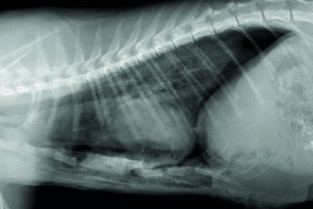

- adopter une méthodologie pour interpréter les affections de la cage thoracique, de la plèvre, du médiastin et des poumons chez les carnivores domestiques ;

- décrire l’aspect normal et anormal de la cage thoracique, de la plèvre, du médiastin et des poumons chez les carnivores domestiques.